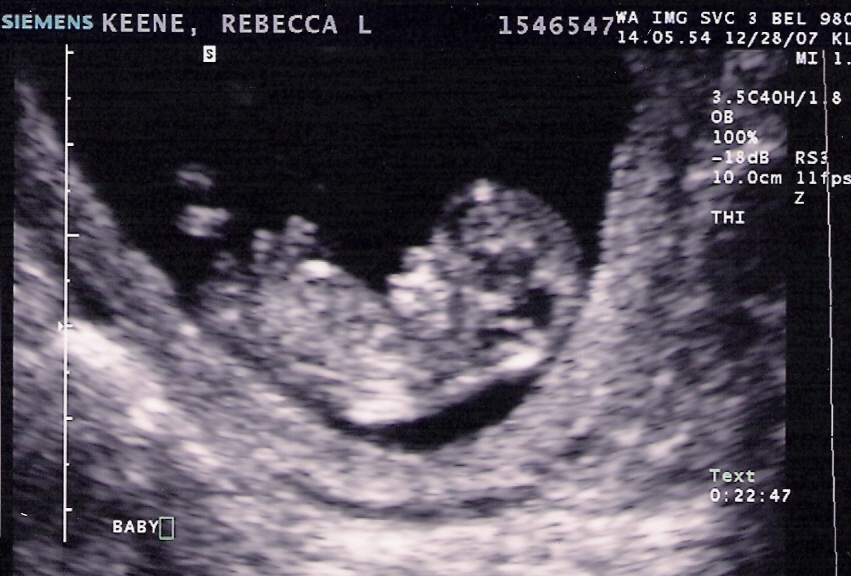

This week we also got the results of our Spina Bifada blood test. Peggy left a message on my cell phone saying, “The results are one in… well, they’re very low.” Tomorrow I will start refinishing the rocking chair my mom gave me that she used to rock me in. It seems as though it will be quite the project, but the nice lady at the hardware store gave me lots of tips.